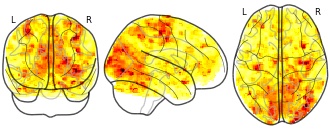

"name": "Multi_VBMgreater_fMRIenhanced",

"description": "Multi-modal analysis in BPD. Brain regions exhibiting greater gray matter and enhanced activation during emotion processing in BPD compared to healthy controls. Note: Results were thresholded at p<.0025. Note2: Results were updated (see Erratum for this publication).",